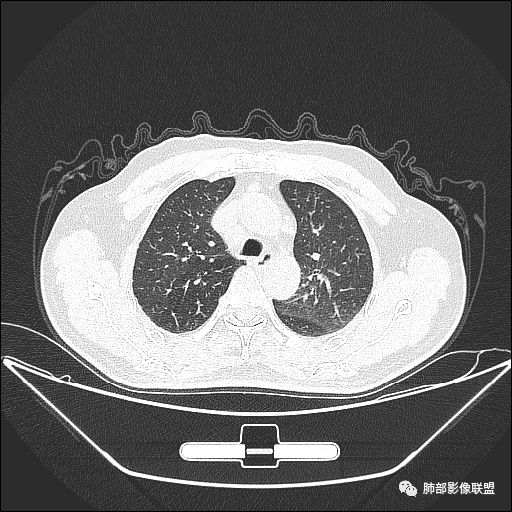

入院CT

老年男性,亚急性病程,咳嗽咳痰。右肺中叶团片影,外朝内分布,大部分边界清楚平直,内侧支气管进入,团片影见低密度坏死区,强化明显,延迟强化,血管破坏不明显,符合爬行征5个特点:

1.肺外周生长。

2.外侧部分体积大于内侧。

3.病变最大径与肺的纵轴及水平面任何一条轴线不平行。

4.病变内侧支气管通畅。

5.病变区域肺容积无缩小。

双侧肺门及纵隔淋巴肿大并可见钙化。考虑结核,但部分边缘膨隆,肿瘤待排。

老年男性,因“咳嗽咳痰1月余。”入院。病程中咳嗽咳痰,咳黄白痰,间断咯少许鲜红色痰血。PPD阳性。胸CT:右肺中叶外侧段支气管管腔阻塞,大片实性病变,病灶边缘光滑,部分边缘膨隆,可见分叶,肺门及纵隔可见肿大淋巴结,并可见钙化。增强可见病灶明显强化,而且延迟强化明显,病灶内多发低密度区,内见血管影,血管变细、部分血管破坏。考虑恶性病变可能性大,鉴别慢性肉芽肿性病变。

右肺中叶外侧段管腔阻塞、实性病变,病灶边缘光滑,可见分叶,肺门及纵隔可见肿大淋巴结,并可见钙化。增强可见病灶内多发低密度区。

老年男性,咳嗽、咳痰1月余,间断血痰。PPD阳性。

胸CT:跨叶大肿块,主体在中叶,右中叶外侧段支气管阻塞,病灶部分边缘膨隆,可见分叶,部分边缘平直,肺门及纵隔可见肿大淋巴结。增强病灶不均匀强化,延迟强化明显,病灶内多发低密度区,内见血管飘浮,部分血管变细、模糊。考虑:恶性病变可能性大,大细胞?淋巴瘤?鉴别慢性肉芽肿性病变。

右肺中叶软组织肿块,外围向内生长,叶间胸膜向前内移位,肿块近肺门侧跨叶,中叶外侧段支气管截断,密度不均匀,双侧肺门及隆突下见肿大淋巴结,增强后呈中度不均质强化,肺动脉供血,多发坏死区,边界尚清,坏死区域内见结构,结合病史考虑恶性,鉴别诊断1结核,爬行征是沿支气管树分布,外宽,内窄,周围有卫星灶,内气管狭窄后扩张,此例沿叶间胸膜长轴分布,气管有截断,不典型。2炎性肉芽肿,符合的地方下方层面增强后延迟性轻度环形强化,不符临床无发热等急性感染病史,实验室指标不符,病灶周围渗出及慢性炎性改变有,不明显。

主病灶在中叶,但是左肺舌段叶有条索影,陈旧病变。蓝色箭头支气管受压,是淋巴结肿大

主病灶在中叶,但是还有结节状病变在下叶

虽然是一个大的病灶,但是周围是比较散

边缘还有多发小灶

淋巴结肿大,钙化。

病灶明显平直,中央是粘液栓,低密度,分界清楚

综上,考虑炎症,结核。

老年男性,咳嗽一月,间断伴红色血痰

PPD阳性

从临床是否要考虑结核,但这个年龄恶性也是高危

影像上叶后段支气管壁增厚,附近似有淋巴结有气体潴留

左下叶背段小结节,舌段索条,内似有扩张支气管

肺门纵隔多发淋巴结肿大,内有钙化灶

我们现在看主病灶,病灶紧贴叶裂:

我想看冠状位,就是看它长轴、病灶的整体形态

外围大、内带小

这时候我认为支气管最重要

支气管进入其中,远端粘液栓

我认为鉴别:结核?腺癌?